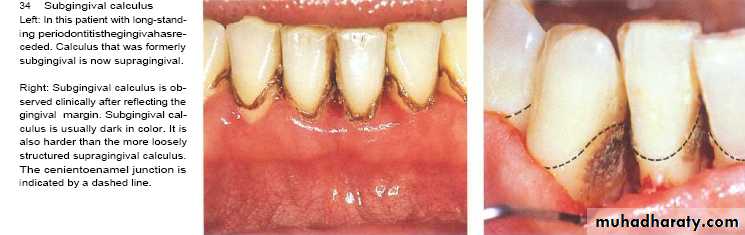

Subgingival calculus

It is usually harder & more tenaciously adhere than supragingival calculus.

It has a brown to black color due to iron pericpetation.

It almost extend to base of pocket but don’t reach juncitional epithelium.

Following gum recession or gingival shrinkage ,it could become supragingival.

• Subgingival calculus

• It is dark color calculus that shines through thin gingival margin.

• It can be seen by reflection of flap during periodental surgery.